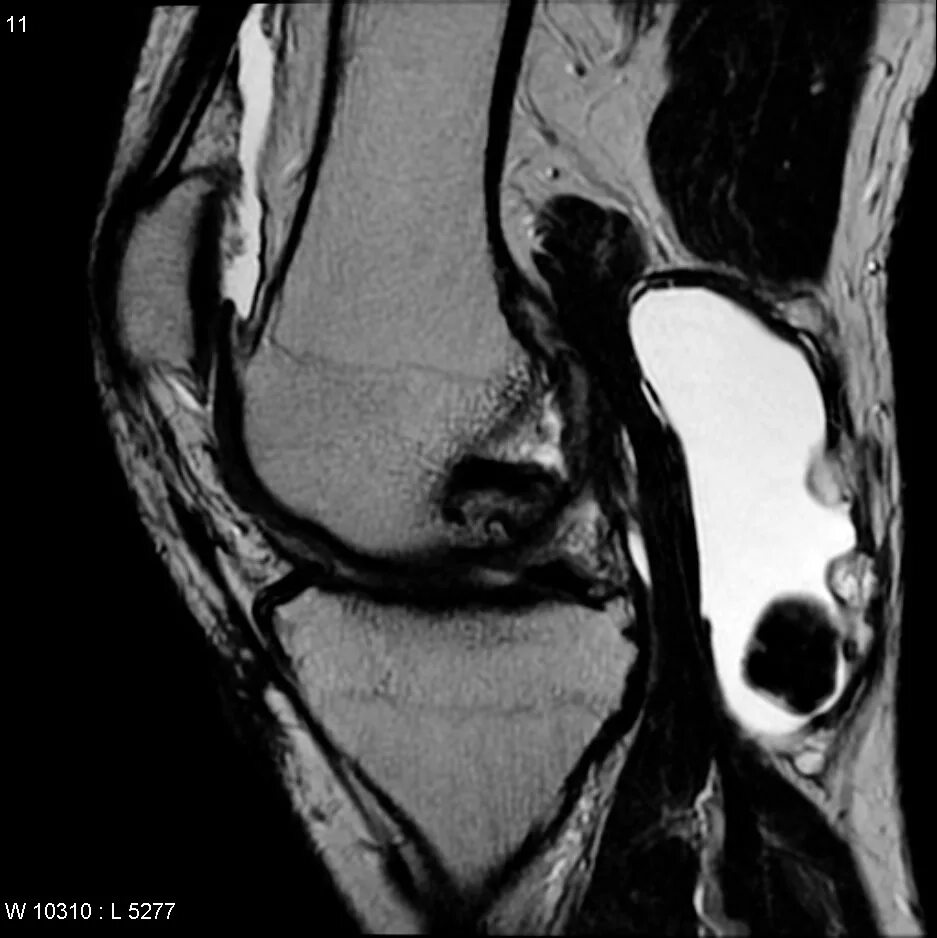

Мрт суставов кемерово